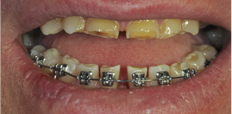

ДО

Пациент обратился с жалобой на истирание передней и боковой групп зубов, отсутствие жевательных зубов, затрудненное пережевывание пищи, ухудшение дикции, появление морщин в уголках рта.